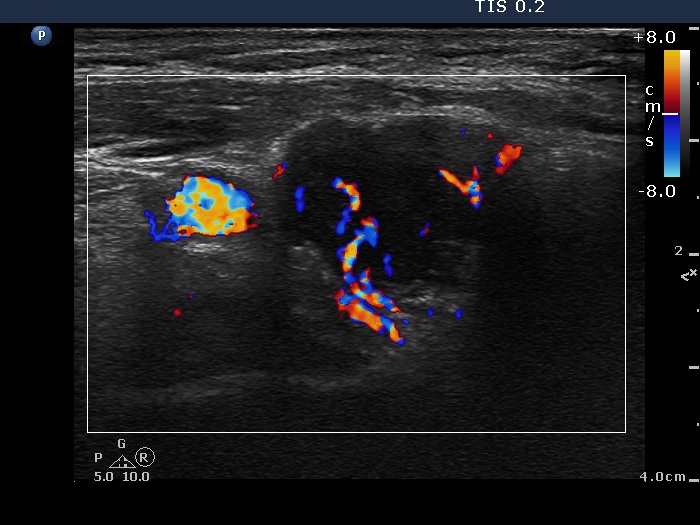

Ultrasonography: The right lobe was hypoechogenic, the left was moderately hypoechogenic. Both lobes were irregular in shape and were composed of several circumscribed areas surrounded with echonormal rim. The vascularization was significantly increased.

The sonographic pattern is specific. At first sight both lobes, particularly the right one seems to be nodular. First, the lobes are composed of a central hypoechogenic part surrounded with an echonormal rim, therefore it seems like the lobes were composed of a large hypoechogenic nodule. Second, connective tissue, perhaps a scar makes an impression in the ventral and in the dorsal part of the right and the left lobe, respectively. This makes an appearance as the lobes were composed of two nodules or one lesion with irregular lobulated and spiculated margins. In fact, the scar is responsible for the irregularities seen on the surface of the hypoechogenic mass, and regarding the hypoechogenic mass, the inclinations are the primary cause.